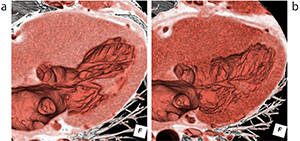

図1 IQonスペクトラルCTとZiostation2によるTAVI弁術後評価 |

Ziostation2では、IQonスペクトラルCTの画像データを取り込み、VR作成やPhyZiodynamicsによる画像解析を行っている。IQonスペクトラルCTでは、Dual EnergyデータをセットにしたSBI(Spectral Based Image)が生成されるが、このデータは専用ワークステーションでしか扱えない。しかし、CT値の定義づけをしたピクセル画像を書き出すことは可能で、このデータをZiostation2に取り込むことでさまざまな処理が可能になる。これによって、仮想単色X線の低keV画像で造影効果を上げた画像を利用して、PhyZiodynamicsを適用して弁留置後のアーチファクトを除去した画像作成などが可能になる。佐々木部長は、IQonスペクトラルCTとZiostation2の組み合わせについて、「Dual Energyの画像を使い慣れたワークステーションで処理できることが一つのメリットです。IQonスペクトラルCTでは心筋評価やSBIのデータを活用した造影剤低減などが可能になっています。最終的にはDual Energyによって精度の高い冠動脈評価が行えるように検討を進めていきます」と述べる。